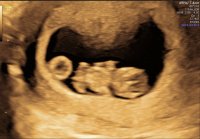

Jeg var ca 5+6 første gangen når hun så bare plommesekken. I dag skal jeg være ca 6+6, hun målte ca 6+4 som hun sa var bra. Og at jeg muligens er ca 6+4/6+5, men kan også være 6+6. Utstyrer er ikke tipp topp, men helt greit.Så deilig utfall

Så ett lite hjerte banke og er så glad for det

. Viste seg å være noen dager bak forventet dato. Så vi bestemte oss for å ikke ta mer blodprøver, heller ny ul neste uke. Og være positive og glede seg over et lite hjerte som banker i magen min